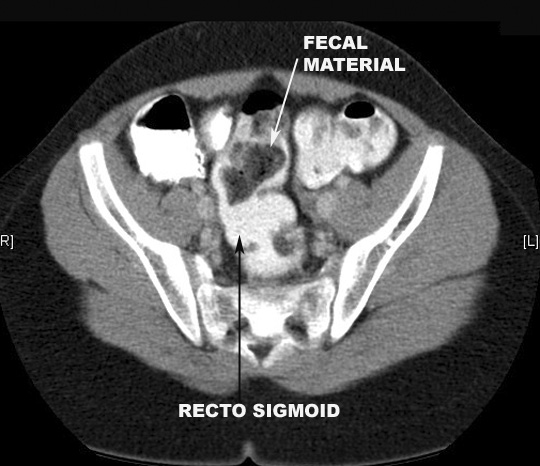

Note the rectosigmoid. Click the image for labeling.